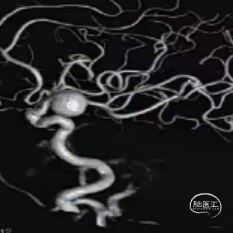

经测量可得动脉瘤宽度平均值为7.0mm,动脉瘤高度为7.4mm,最终选择WEB™ SL 9*6。

动脉瘤远端子囊先进行填圈,近端动脉瘤植入WEB™。

术后6个月影像提示血栓形成,动脉瘤完全闭塞,WEB™完全栓塞。